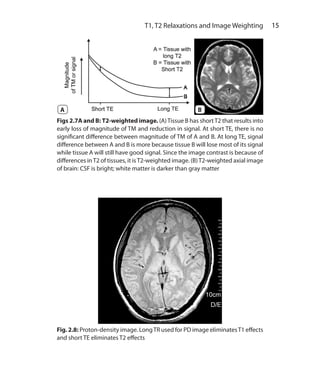

bright on STIR making them easier to pick up.

Ch-5.indd 42 13-09-2012 15:58:20

43 Sequences I: Basic Principles and Classification

Figs 5.8A and B: STIR sequence. (A) When excitatory 90° pulse is applied after

a short TI the magnetization vector of fat reaches zero degrees (along positive

side of Z-axis). As the signal cannot be detected when the vector is vertical along

Z-axis, there is no signal from fat and fat is saturated. (B) STIR coronal image of

the pelvis: note there is suppression of subcutaneous fat

B

A

Ch-5.indd 43 13-09-2012 15:58:20

44  MRI Made Easy (For Beginners)

LONG TI IR Sequence

When 90 degree pulse is applied at longTI, LM of most tissues is almost

fully recovered. Since water has long T1, its LM recovery is at halfway